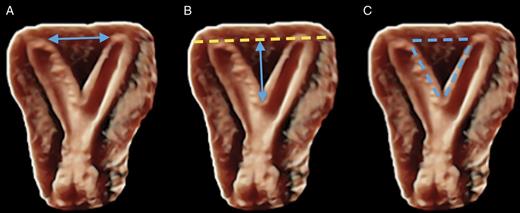

Correct measurements of uterine fundal internal indentation depth and angle: an important but overlooked issue for precise diagnosis of uterine anomalies

Więcej

Congenital Uterine Malformation by Experts (CUME): better criteria for distinguishing between normal/arcuate and septate uterus?